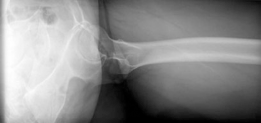

Standard preoperative imaging must include an anteroposterior (AP) pelvis, cross-table lateral, and false-profile view of the affected hip. These evaluate for dysplasia, impingement morphology (cam/pincer), and degenerative changes.

Magnetic Resonance Arthrography (MRA) is the gold standard for evaluating the capsuloligamentous complex. Extravasation of contrast anteriorly often delineates the size and location of the capsular defect. MRA also assesses labral integrity, chondral damage, and the viability of the femoral head. A 3D computed tomography (CT) scan is highly recommended to quantify femoral anteversion and acetabular version, as unrecognized osseous malorientation (e.g., severe femoral retroversion) will predispose the reconstruction to failure if not addressed concurrently with a derotational osteotomy.

Capsulotomy and Joint Evaluation

A Z-shaped capsulotomy is typically performed, though in cases of severe capsular deficiency, the surgeon may encounter a massive defect with dense scar tissue. The remaining capsular edges are tagged with heavy non-absorbable sutures. The hip is dislocated anteriorly by externally rotating and flexing the leg. The ligamentum teres is sharply excised if intact. The femoral head and acetabulum are inspected for chondral defects, and any concurrent intra-articular pathology (e.g., labral tears, cam lesions) is addressed at this stage.